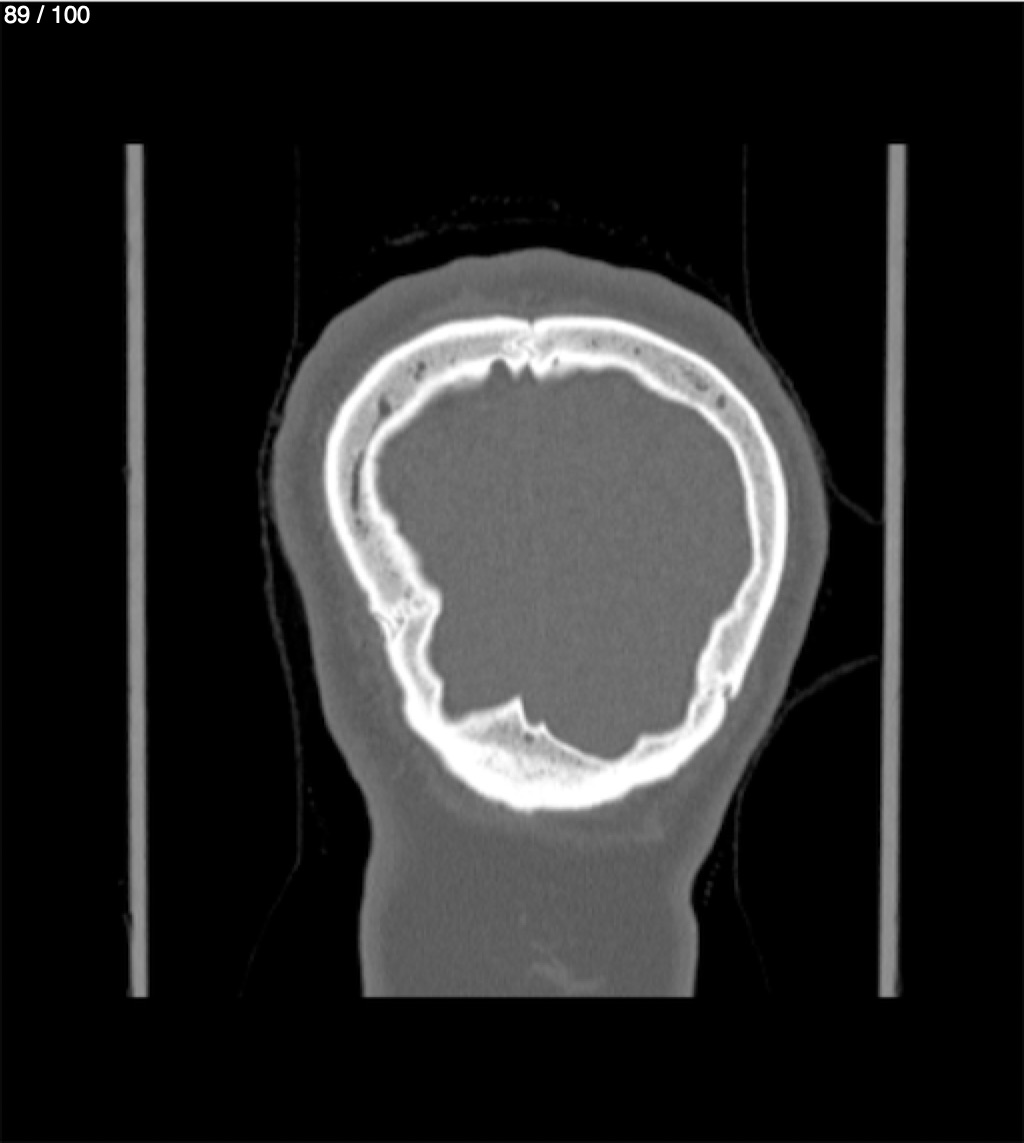

Yonelly Barrios Diaz 35A - T.C Craneo